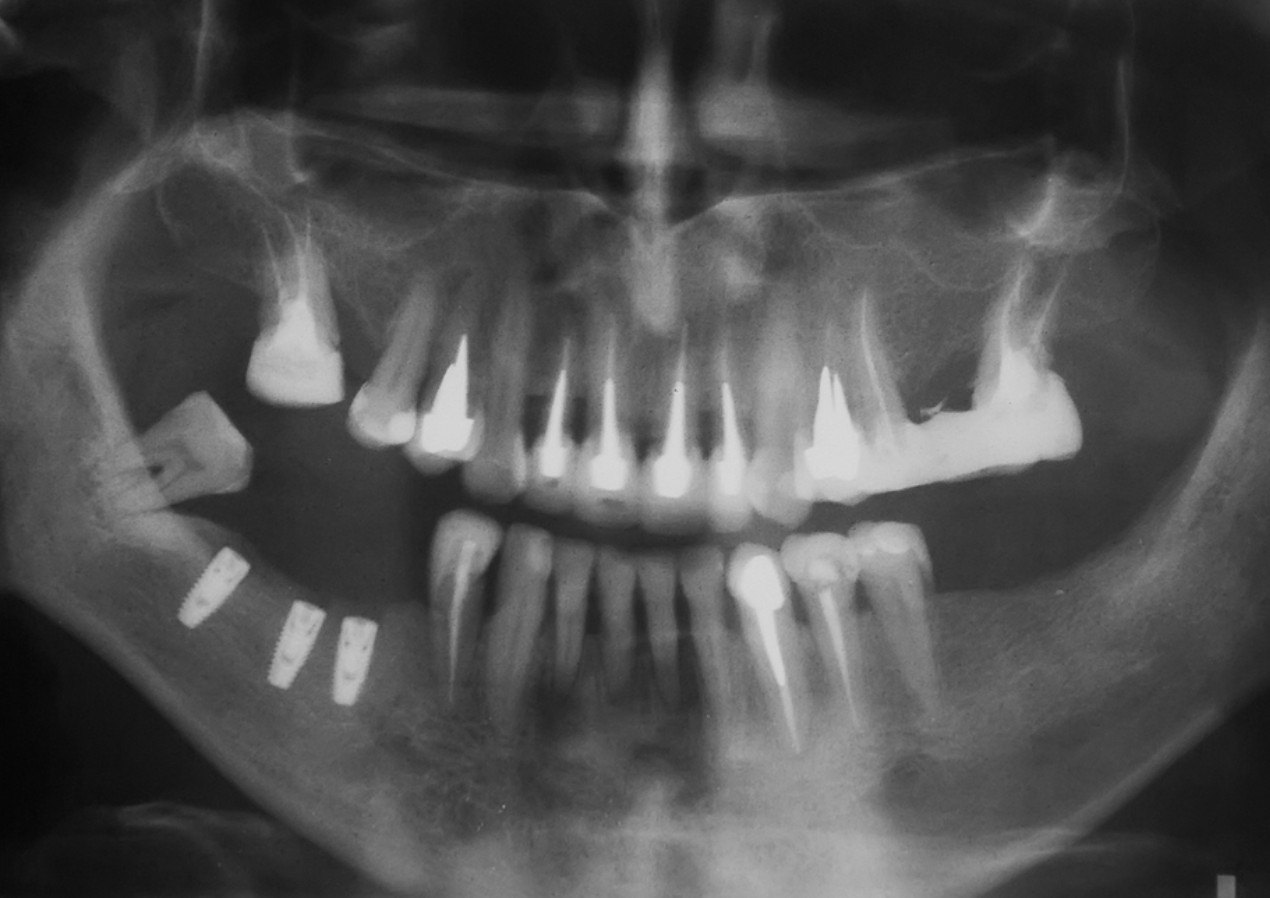

A dental implant is a titanium substitute for the tooth root that is missing. During a surgical procedure, the metal implant, which looks like a screw or a cylinder, is placed directly into the upper or lower jawbone. Over the course of several months, the implant integrates into the surrounding bone, making it stable enough to support a crown. During this healing process, a temporary tooth replacement option can be worn over the implant sites. Once the implant has integrated into the bone, an impression is taken to create a permanent crown that sits on top of the implant.

Ideally, candidates for dental implants will be in good general and oral health. Since the implant is inserted directly into the jaw, candidates for the procedure must have adequate bone density in the jaw to support the implant. Dental implants are connected with the gum tissues and underlying bone in the mouth, so candidates should also have healthy gums that are free of periodontal disease.